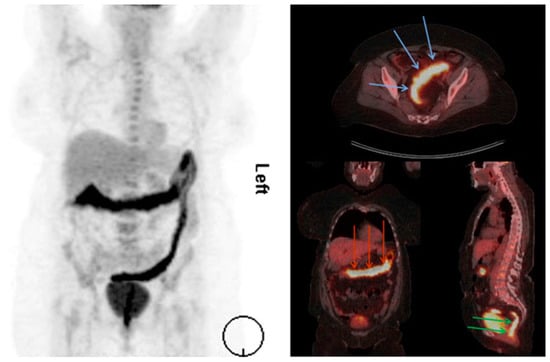

- Bettenworth, D.; Reuter, S.; Hermann, S.; Weckesser, M.; Kerstiens, L.; Stratis, A.; Nowacki, T.M.; Ross, M.; Lenze, F.; Edemir, B.; et al. Translational 18F-FDG PET/CT imaging to monitor lesion activity in intestinal inflammation. J. Nucl. Med. 2013, 54, 748–755. [Google Scholar] [CrossRef]

- Malham, M.; Hess, S.; Nielsen, R.G.; Husby, S.; Hoilund-Carlsen, P.F. PET/CT in the diagnosis of inflammatory bowel disease in pediatric patients: A review. Am. J. Nucl. Med. Mol. Imaging 2014, 4, 225–230. [Google Scholar]

- Skehan, S.J.; Issenman, R.; Mernagh, J.; Nahmias, C.; Jacobson, K. 18F-fluorodeoxyglucose positron tomography in diagnosis of paediatric inflammatory bowel disease. Lancet 1999, 354, 836–837. [Google Scholar] [CrossRef]

- Loffler, M.; Weckesser, M.; Franzius, C.; Schober, O.; Zimmer, K.P. High diagnostic value of 18F-FDG-PET in pediatric patients with chronic inflammatory bowel disease. Ann. N. Y. Acad. Sci. 2006, 1072, 379–385. [Google Scholar] [CrossRef] [PubMed]

- Perlman, S.B.; Hall, B.S.; Reichelderfer, M. PET/CT imaging of inflammatory bowel disease. Semin. Nucl. Med. 2013, 43, 420–426. [Google Scholar] [CrossRef] [PubMed]

- Neurath, M.F.; Vehling, D.; Schunk, K.; Holtmann, M.; Brockmann, H.; Helisch, A.; Orth, T.; Schreckenberger, M.; Galle, P.R.; Bartenstein, P. Noninvasive assessment of Crohn’s disease activity: A comparison of 18F-fluorodeoxyglucose positron emission tomography, hydromagnetic resonance imaging, and granulocyte scintigraphy with labeled antibodies. Am. J. Gastroenterol. 2002, 97, 1978–1985. [Google Scholar] [CrossRef] [PubMed]

- Meisner, R.S.; Spier, B.J.; Einarsson, S.; Roberson, E.N.; Perlman, S.B.; Bianco, J.A.; Taylor, A.J.; Einstein, M.; Jaskowiak, C.J.; Massoth, K.M.; et al. Pilot study using PET/CT as a novel, noninvasive assessment of disease activity in inflammatory bowel disease. Inflamm. Bowel Dis. 2007, 13, 993–1000. [Google Scholar] [CrossRef]

- Louis, E.; Ancion, G.; Colard, A.; Spote, V.; Belaiche, J.; Hustinx, R. Noninvasive assessment of Crohn’s disease intestinal lesions with (18) F-FDG PET/CT. J. Nucl. Med. 2007, 48, 1053–1059. [Google Scholar] [CrossRef]

- Das, C.J.; Makharia, G.; Kumar, R.; Chawla, M.; Goswami, P.; Sharma, R.; Malhotra, A. PET-CT enteroclysis: A new technique for evaluation of inflammatory diseases of the intestine. Eur. J. Nucl. Med. Mol. Imaging 2007, 34, 2106–2114. [Google Scholar] [CrossRef]

- Agriantonis, D.; Perlman, S.B.; Spier, B.J.; Jaskowiak, C.J.; Reichelderfer, M. FDG PET/CT aids the management of IBD patients suspected of disease flare-up. J. Nucl. Med. 2008, 49 (Suppl. S1). [Google Scholar]